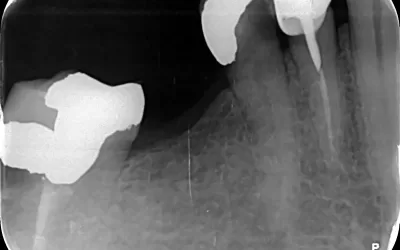

بارداری به دلیل تغییرات هورمونی میتواند سلامت دهان و دندان را تحت تأثیر قرار دهد. التهاب لثه، پوسیدگیهای پیشرفته و حتی عفونت دندانی در این دوران شایعتر است. در شرایطی مثل نیاز به عصبکشی دندان یا حتی کشیدن دندان، گرفتن عکس دندان برای تعیین عمق پوسیدگی یا بررسی وضعیت ریشه ضروری است. اگر این عفونتها درمان نشوند، میتوانند برای سلامت مادر و جنین خطرناکتر از خود عکسبرداری باشند.

اشعهای که در رادیوگرافی دندان استفاده میشود بسیار کم است و به طور مستقیم به جنین نمیرسد. استفاده از دستگاههای دیجیتال امروزی، میزان اشعه را به حداقل میرساند. همچنین در کلینیکهایی مثل کلینیک دندانپزشکی زاگرس، از پیشبند سربی مخصوص برای محافظت از شکم و تیروئید استفاده میشود تا هیچ نگرانی برای مادر وجود نداشته باشد. در نتیجه، اگر نیاز به درمان فوری باشد، عکسبرداری دندان بیخطر محسوب میشود.

بر اساس مطالعات، میزان اشعه رادیوگرافی دندان بسیار کمتر از آستانهای است که میتواند به جنین آسیب برساند. به همین دلیل، اگر همه موارد احتیاطی رعایت شود، عکسبرداری دندان در بارداری خطری ندارد. در واقع، عفونتهای درماننشده دندانی، تهدید جدیتری برای سلامت جنین نسبت به اشعه ایکس محسوب میشوند.